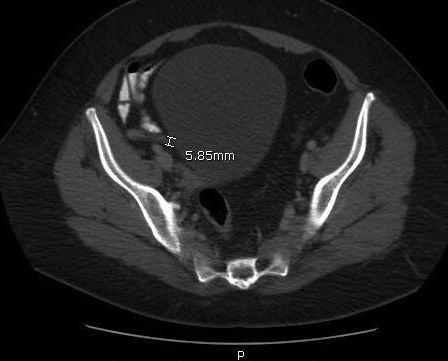

A computed tomography (CT) scan of the abdomen and pelvis with oral and intravenous contrast identified contrast in the base of the appendix but not the tip (Figures). The tip appeared mildly thickened, measuring approximately 6 to 9 mm, with hazy infiltrative change adjacent to it. Numerous clustered subcentimeter lymph nodes in the right lower quadrant also were identified, making the diagnosis consistent with acute appendicitis.